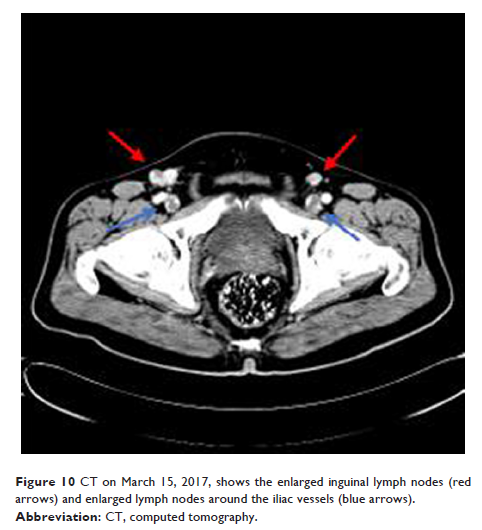

男性腹壁副乳腺癌一例并文献复习